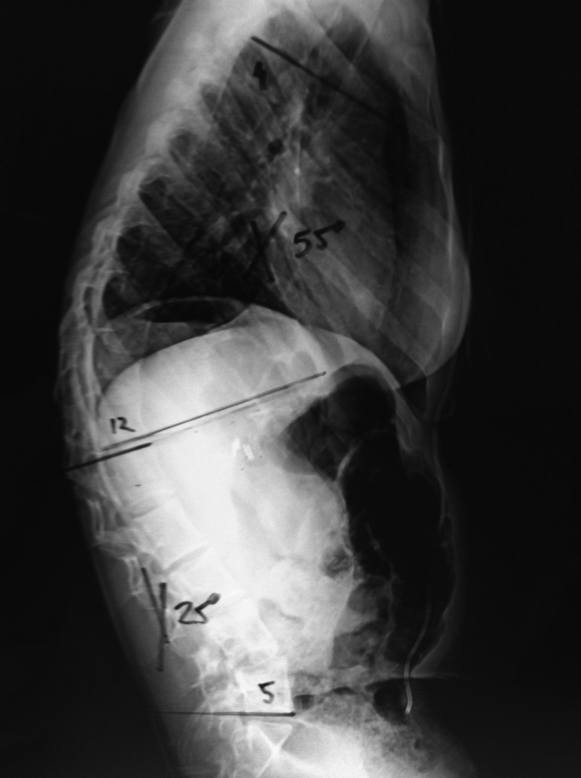

O diagnóstico da escoliose neuromuscular é feito inicialmente clinicamente, através de uma boa anamnese e exame físico.  Os exames de imagem como a radiografia da coluna vertebral e ressonância magnética são importantes para a decisão terapêutica.

Além disso, métodos como radiografias e tomografia, além de ressonâncias, dão maiores detalhes para que o ortopedista consiga ter uma boa avaliação.